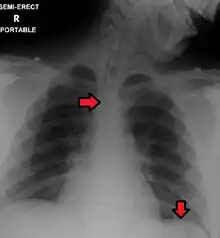

Great care must be taken to ensure that the tube has not passed through the larynx into the trachea and down into the bronchi. The reliable method is to aspirate some fluid from the tube with a syringe. This fluid is then tested with pH paper (note not litmus paper) to determine the acidity of the fluid. If the pH is 4 or below then the tube is in the correct position. If this is not possible then correct verification of tube position is obtained with an X-ray of the chest/abdomen. This is the most reliable means of ensuring proper placement of an NG tube.[11] The use of a chest x-ray to confirm position is the expected standard in the UK, with Dr/ physician review and confirmation. Future techniques may include measuring the concentration of enzymes such as trypsin, pepsin, and bilirubin to confirm the correct placement of the NG tube. As enzyme testing becomes more practical, allowing measurements to be taken quickly and cheaply at the bedside, this technique may be used in combination with pH testing as an effective, less harmful replacement of X-ray confirmation.[12] If the tube is to remain in place then a tube position check is recommended before each feed and at least once per day.

Complications with nasogastric intubation can occur due to incorrect initial placement of the nasogastric tube or due to changes in tube position that go unrecognized. Nasogastric tubes mistakenly placed in the trachea or lungs can lead to aspiration of enteral feeds or medications administered through the NG tube. This can also lead to pneumothorax or pleural effusion, which often requires a chest tube to drain. [15][4] Nasogastric tubes can also be mistakenly placed within the intracranial space; this is more likely to occur in patient who already have specific types of skull fractures. [4]